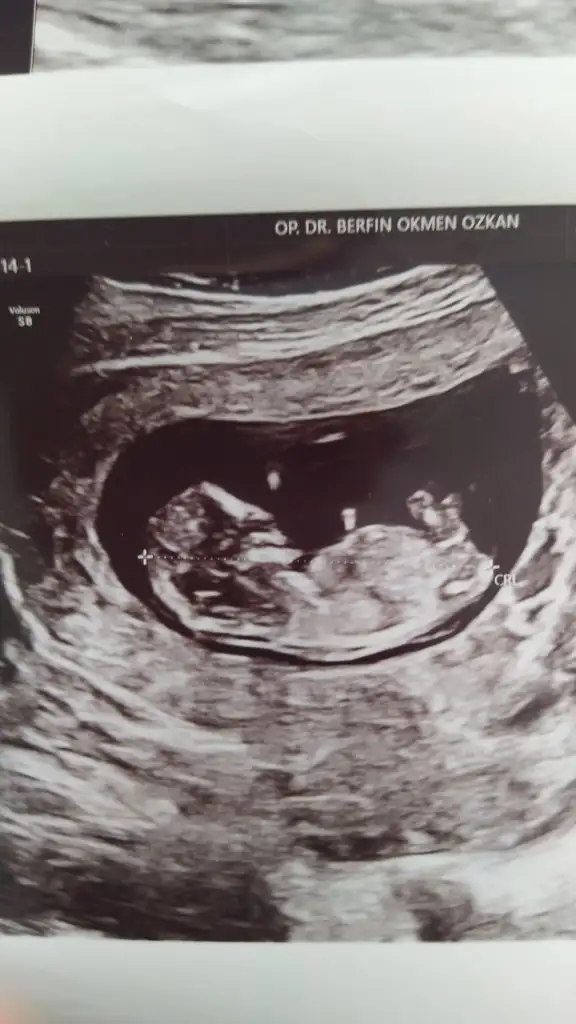

• 20210613_193300.webp

20210613_193300.webp

29,1 KB · Görüntüleme: 58

• 20210612_111002.webp

20210612_111002.webp

35,6 KB · Görüntüleme: 49

29,1 KB · Görüntüleme: 44

• 20210613_193211.webp

20210613_193211.webp

47,8 KB · Görüntüleme: 44

• 20210525_145025.webp

20210525_145025.webp

24,6 KB · Görüntüleme: 48

Tahmin etmiştiniz ama tutmadı :)) sorun değil zaten eğlence amaçlı olduğunu düşünüyorum. Zaten 2 ihtimal var :)) teşekkürler yine de.